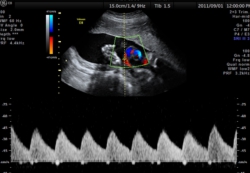

STIC機能は,Volumeデータから心拍数を推定し1心拍分の動画像を再構築し,直交三断面やレンダリング画像を表示します。任意断面の観察,解析,計測等が可能であり、胎児心エコー検査を強力にサポートします。

臍帯血流をパルスドプラで途絶や逆流を評価する事により、胎児胎盤循環不全などの早期検出が可能となります。更に子宮内胎児発育遅延(IUGR)の成否判断の強力なツールとなります。